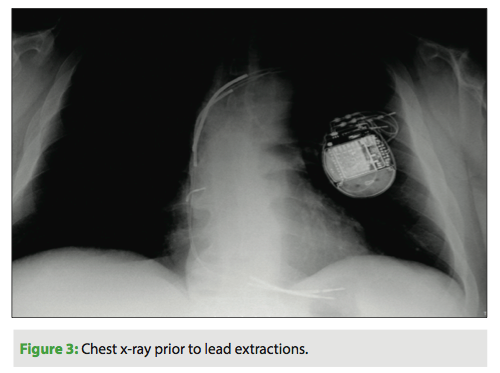

Additionally, he had congenital thrombocytopenia and a history of acute renal failure. In 2010 his ICD lead failed, and he underwent an RV lead revision and generator change. The original RV lead was retained and capped. In 2012 he developed Group B Strep Bacteremia, and underwent full system extraction and reimplantation. He now presents with recurrent bacteremia positive for Group B Strep. Our recommended plan of action was to extract all of his current hardware (Figure 3) and reimplant with an S-ICD.

It is recommended that extractions should always be done by an experienced extractor. At Deborah Heart and Lung Center, the EP department extracts more than 200 leads per year. This extraction was performed in our new hybrid OR. Post-extraction procedure, a portion of the existing RV lead remained and was later removed via a femoral snare approach (Figure 4).